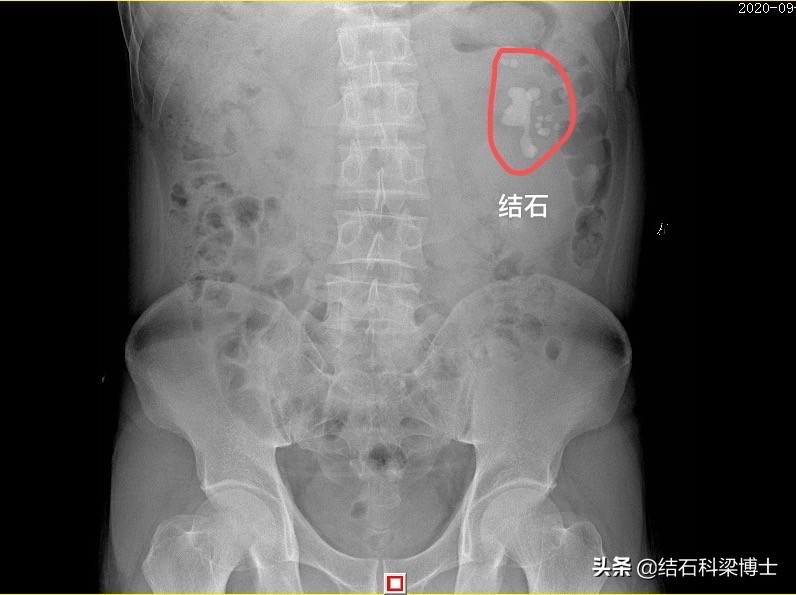

DR片可见肾结石巨大且多发